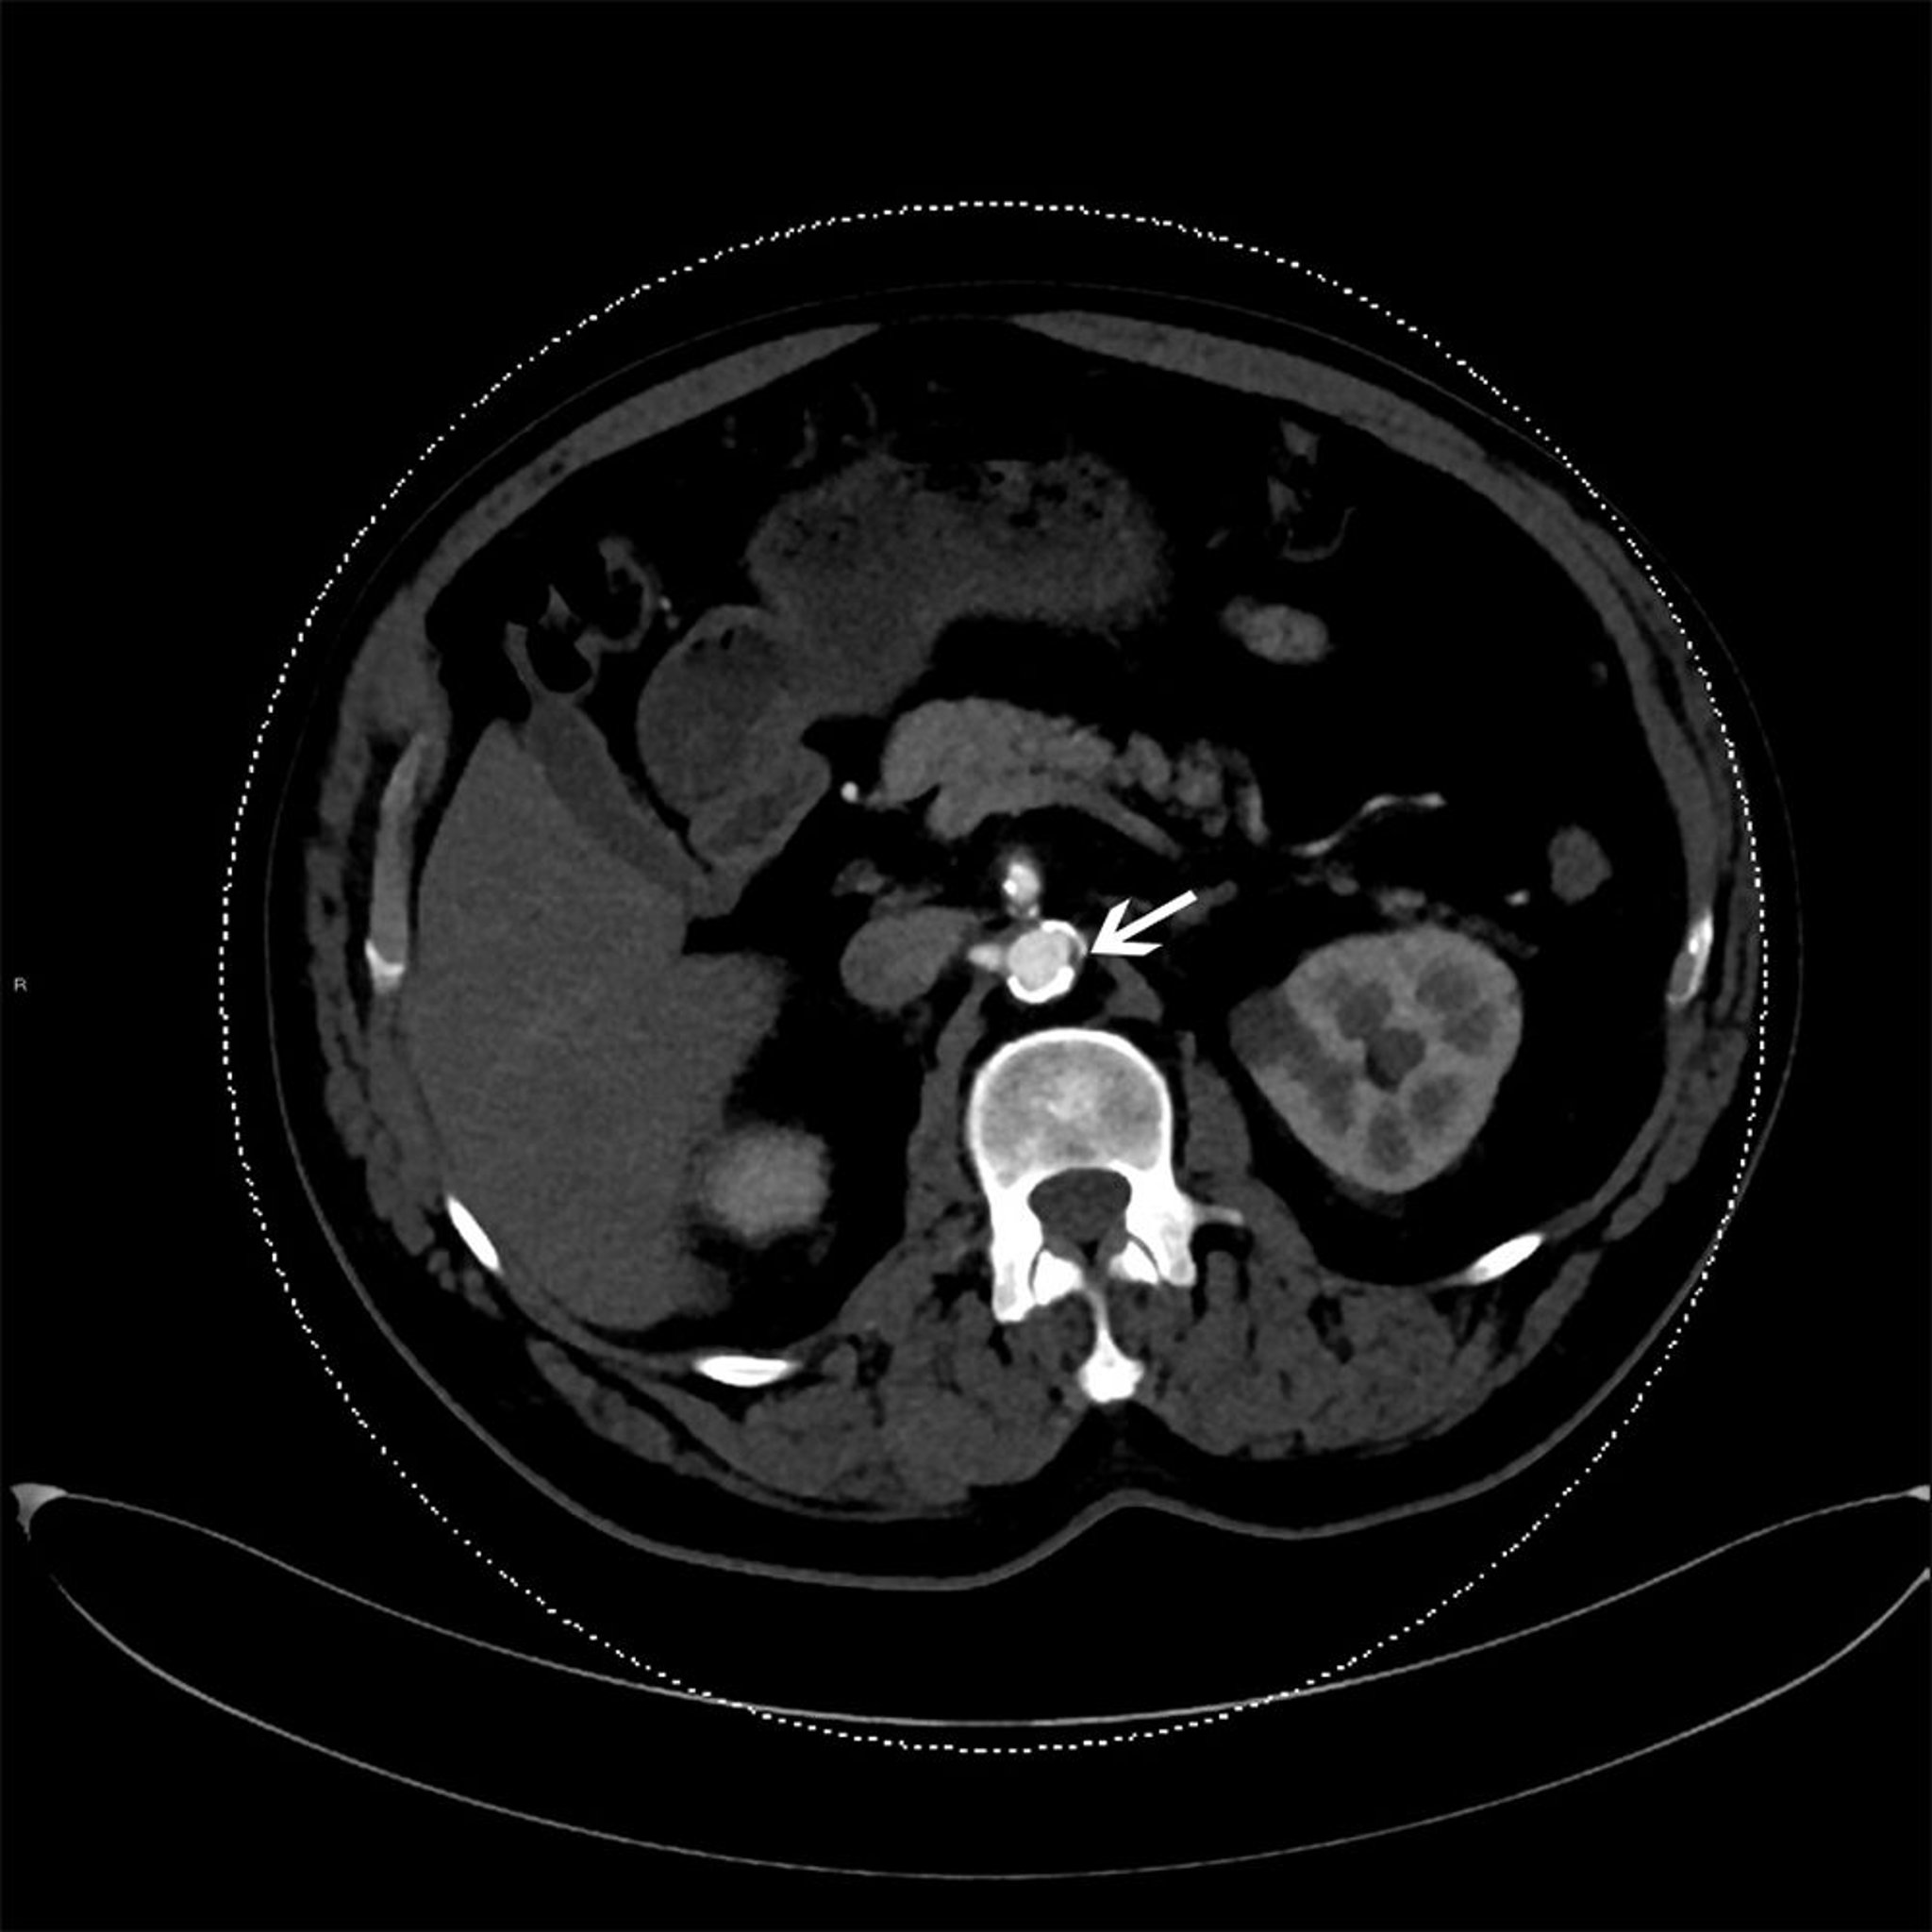

Plaque athéroscléreuse dans l'aorte descendante

Cette TDM avec contraste montre une plaque d'athérosclérose dans l'aorte descendante (flèche).